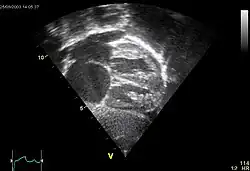

![]() Echokardiograficzny obraz ubytku w przegrodzie międzyprzedsionkowej typu II |

Ubytek w przegrodzie międzyprzedsionkowej (ang. atrial septal defect, ASD) – jedna z najczęstszych wrodzonych wad serca, stanowiąca 3–14% wad serca pod postacią jednego lub więcej otworów w przegrodzie międzyprzedsionkowej powodujących przeciek lewo-prawy. Najczęściej jest wadą izolowaną[1].